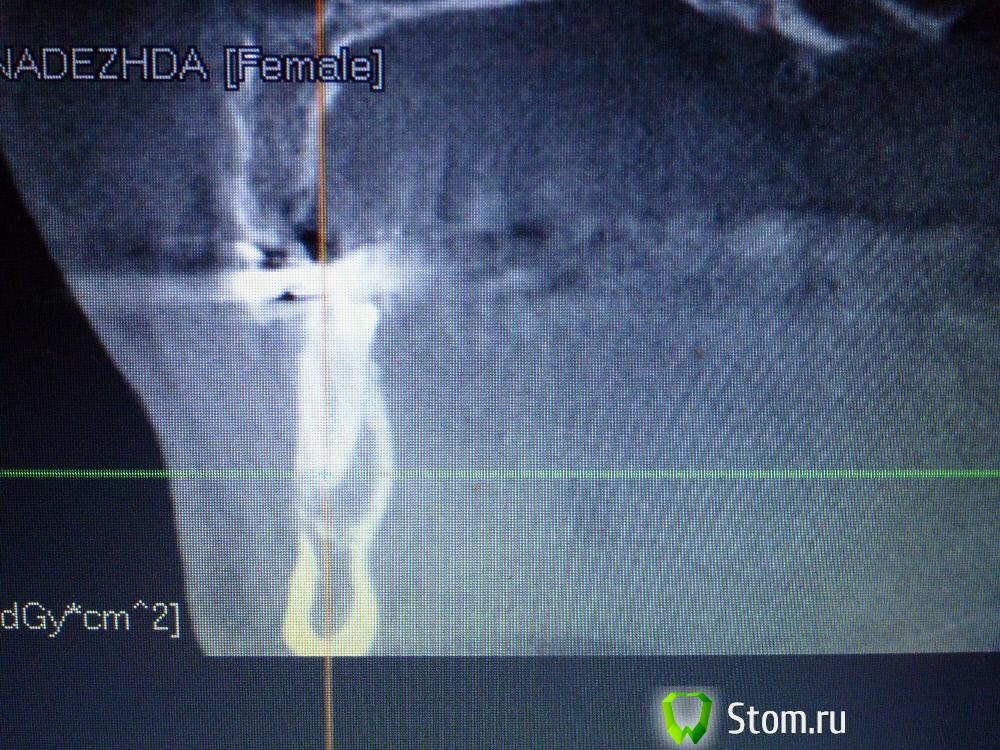

IvanK Опубликовано 25 ноября, 2011 Поделиться Опубликовано 25 ноября, 2011 Коллеги , посоветуйте Ваш план лечения.Пациентка обратилась с целью протезирования. Была направлена на ОПТГ. Обнаружены "кисты".Предположены амелобластома или первичная киста. Направлена на кафедру в 1 мед. Сказали, что "обычные кисты".Вижу 2 варианта:1). эндодонтическое лечение, цистэктомия, гистология, резекция верхушек корней, наблюдение, далее костная пластика?, имплантация. 2) Удаление зубов с периапикальными изменениями + 8-ка, гистология, пластика, имплантация боковых отделов. Ссылка на комментарий

IvanK Опубликовано 25 ноября, 2011 Автор Поделиться Опубликовано 25 ноября, 2011 Сразу прошу прощение за качество фотографий Ссылка на комментарий

Corvalus Опубликовано 26 ноября, 2011 Поделиться Опубликовано 26 ноября, 2011 Эндодонтическое лечение: 45,44,33-го тоже он в зоне кисты,34,36. Хуже дела обстоят с 35-м, глянуть бы прицельный снимок, если периапикальные изменения есть, то шуруп трудно достать будет. Обязательно реэндодонтия 43. Далее цистэктомия без всяких резекций с обязательной гистологией. Заполнять кисты не стал бы, достаточно крови, очаг гнойный. Через несколько недель парадонтологическое лечение, после костная пластика с отсроченной имплантацией. И в конце рациональное протезирование одиночными коронками. При нормальном эндодонтическом лечении рецедива кист не должно быть, а если и будет, то не на всех зубах сразу. Себе зубы удалять не стал бы, опыт лечения таких зубов есть, с имплантацией всегда решить можно по ходу поступления проблем. Второй вариант имеет место быть. Объяснить пациентке все за и против, пусть сама выбирает. Ссылка на комментарий